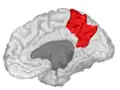

Precuneus of left cerebral hemisphere (shown in red). -

Precuneus of right cerebral hemisphere. -